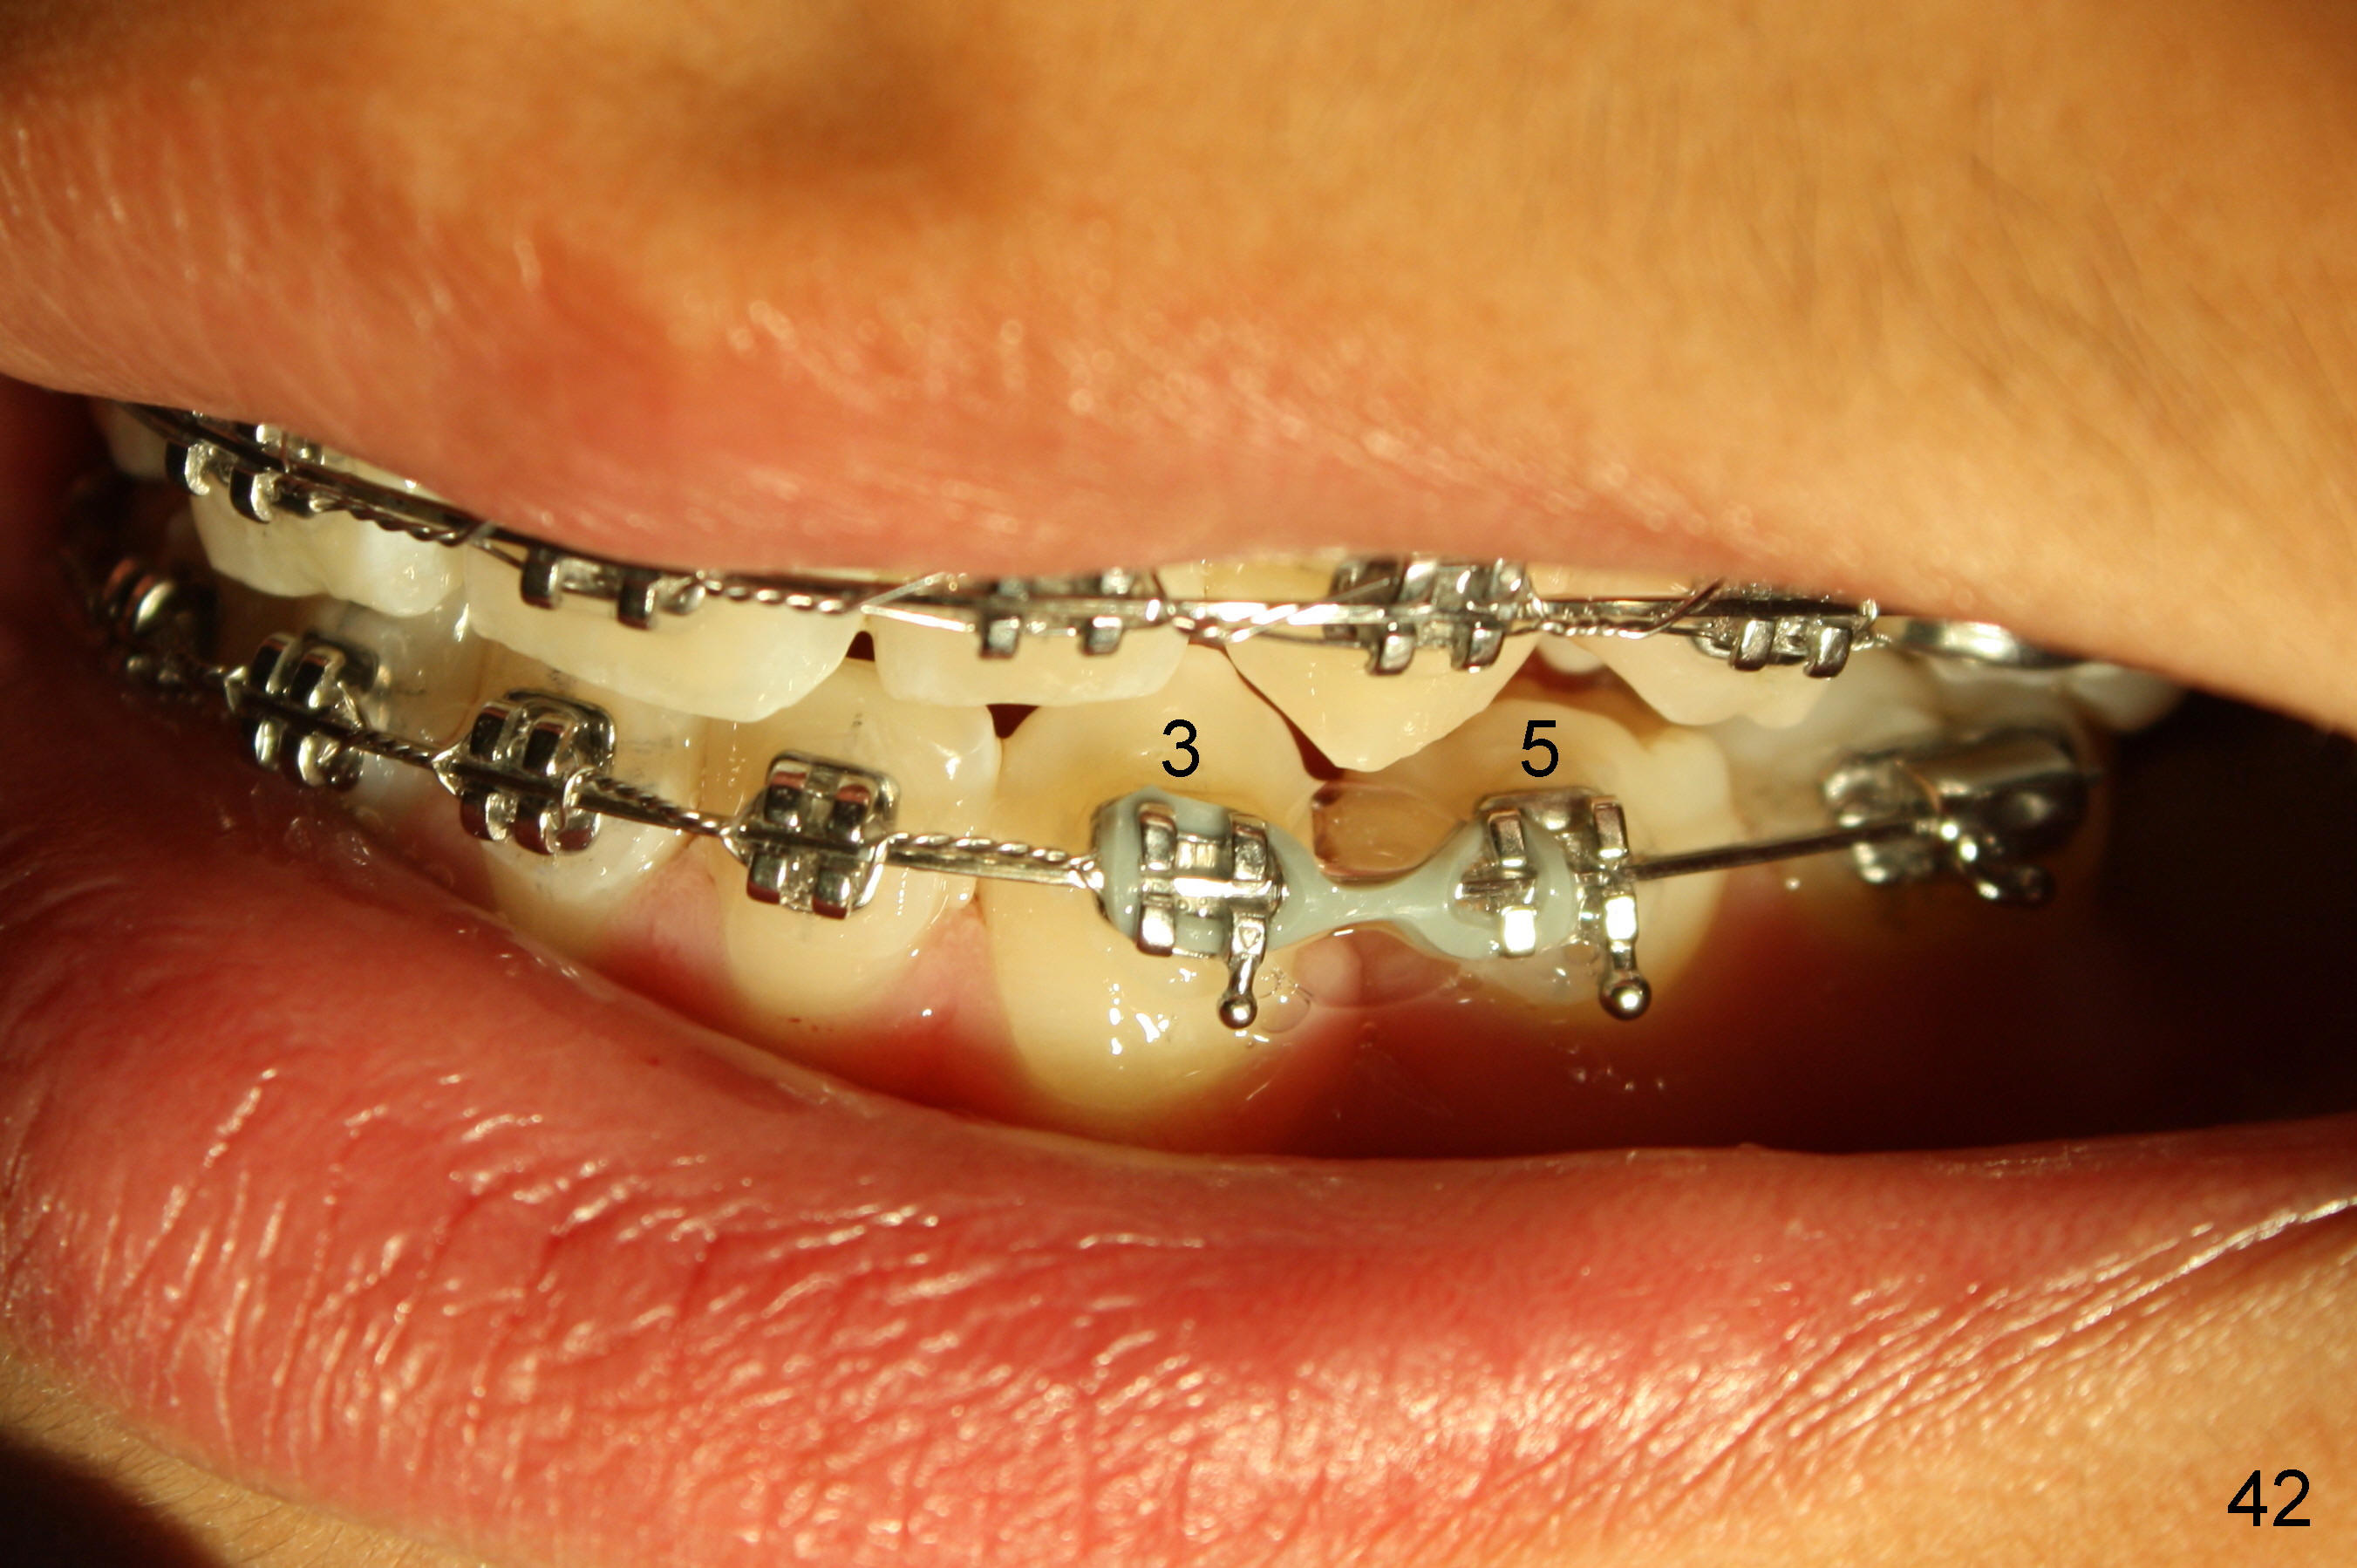

Prior to bracketing, the mesiodistal space for #18 is planned to be obtained by moving #20 and then #19 mesially (Fig.31-35, 16x16 ss). The six anterior lower teeth are tied together in a figure 8 fashion. Power chains are placed between the lower canine and the 2nd bicuspids. The upper diastemata are to be closed by power chains between the 1st molars.

The kid returns 1 month 10 days after last visit. Wires change to 16x22 ss with figure-8 wires placed between UR3 and UL4 and between LL3 and LR 4 (Fig.41-45). A separator is placed between LL6 and 7.